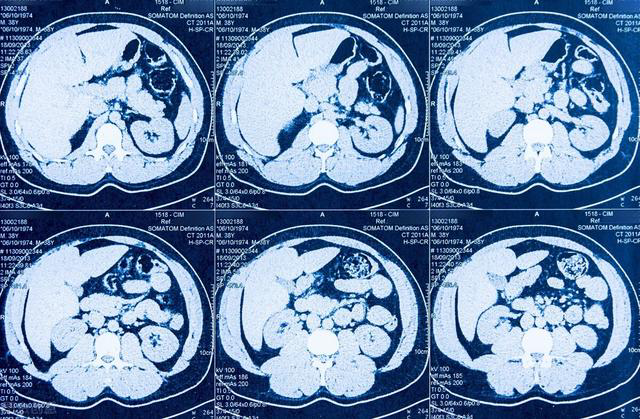

CT成像的基本原理主要包括:CT是用X线束对人体检查部位一定厚度的层面进行扫描,由探测器接收该层面上各个不同方向的人体组织对X 线的衰减值,通过计算机处理后得到。用黑白不同的灰度等级在荧光屏上显示出来,即构成CT图像。

图源:网络

头颅CT:能发现脑出血、脑梗死、脑肿瘤、脑萎缩、颅脑外伤引起的骨折血肿、鼻窦炎、鼻咽癌等;

胸部CT:能发现肺癌、肺结核、胸主动脉瘤等;

腹部CT:能分辨肝内占位性病变的性质,诊断肝硬化、胆道疾病、胰腺癌、胰腺炎、肾脏肿瘤、膀胱肿瘤、妇科肿瘤、前列腺肿瘤等;

脊柱和骨关节CT:对椎间盘膨出、脱出、椎管狭窄的诊断率明显高于普通的X光照片,对骨肿瘤的诊断率也明显增高。

优点:可以断层看,经处理后可以显示更多信息。

缺点:辐射大于X线,对于脑部、脊髓、实质脏器等,CT成像不如核磁检查清晰。